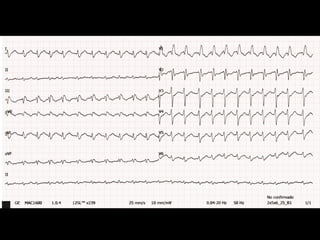

•  DiagnósAco

–  IAM	con	SDST	inferior	+	BAVC

•  Nombre	la	pared	afectada	y	probable	arteria	culpable

–  	Pared	inferior.	Arteria	coronaria	derecha	(ACD)

•  ¿Qué	derivadas	complementarias	solicitaría	y	qué	hallazgos	podría	encontrar?

–  Derivadas	derechas

–  SDST	en	precordiales	derechas

•  ¿Cuál	es	el	trastorno	del	ritmo	y	explique	a	qué	se	puede	deber?

–  BAVC

–  Compromiso	de	la	rama	del	nodo	AV	de	la	ACD

•  ¿Qué	medidas	terapéuAcas	indicaría?

–  Reperfusión	por	medio	más	expedito

–  Volemización

–  Preparar	MP	transitorio

•  	¿Qué	medidas	terapéuAcas	no	indicaría	de	inicio?

–  Nitratos

–  Morfina

–  Obviamente:	iECAs,	B-Bloqueo